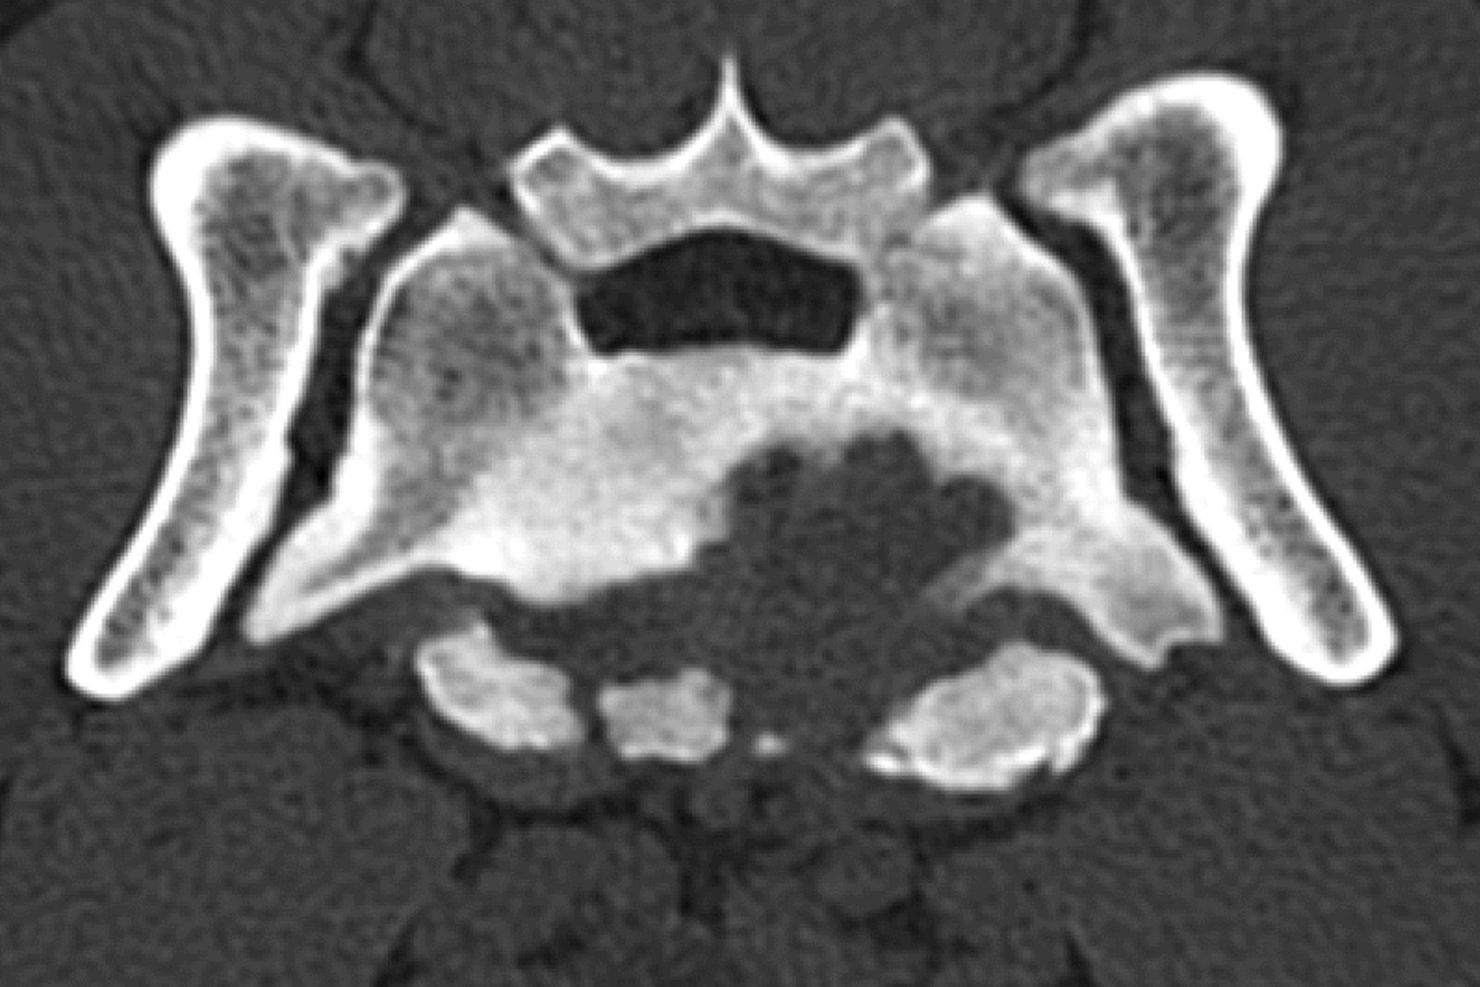

Zentral ist für mich lumbosakraler Druckschmerz bei Palpation in Kombination mit dem Vorstellungsgrund „Möchte nicht mehr springen / Stiegen steigen / ballspielen“ oder einer leichten Lahmheit. Wichtig ist es, sowohl eine neurologische als auch eine orthopädische Untersuchung durchzuführen, da die Symptome eben nicht charakteristisch für eine neurologische Erkrankung sind. Der Ausschluss von orthopädischen Problemen ist sehr wichtig – da ältere Patienten betroffen sind, kann es sein, dass beide Probleme vorliegen. Das erschwert die Diagnosestellung und man braucht weitere Schritte zur Bestätigung. Röntgenbilder können die Verdachtsdiagnose erhärten, aber nicht bestätigen. Um sie zu bestätigen, braucht man schnittbildgebende Verfahren wie etwa CT oder MRT.